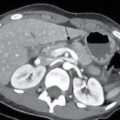

Malakoplakia is a chronic granulomatous multisystemic disease characterized by the presence of one or more white plaques in various organs of the body, preceded by chronic bacterial infection. In most of the reported cases, it was found that E. coli contributes to 80%. Malakoplakia originates from the Greek words, malakos (plaque) and pakos (soft). Malakoplakia affects many organ systems including gastrointestinal tract, lungs, bone, skin and lymph nodes. The urinary tract is frequently involved and all parts of urinary tract can be affected while the second most common site is kidneys. Patients with this pathology may be asymptomatic or show nonspecific symptoms, such as fever, pain, haematuria, renal failure and persistent UTI. The prevalence is unknown. It occurs predominantly in the female sex, with a ratio of 4:1 and the average age of diagnosis is at 50 years. It rarely occurs in paediatric ages. Most commonly seen in immunocompromised patients about 40%, which include posttransplant HIV/AIDS, lymphoma, poorly controlled diabetes, steroid therapy or alcoholism. With regard to urinary tract involvement, in 64% of cases the disease will affect both kidneys. Gram-negative bacteria are frequently associated with malakoplakia with E. coli found in at least two-thirds of lesions. In addition to this microorganism, other possible ones are described, such as Klebsiella, Proteus, Mycobacterium, Staphylococcus and fungi, which release cytokines and produce inflammation and kidney damage. Michaelis-Gutmann bodies are pathognomonic for the disease. They differentiate it from two similar processes which are megalocytic interstitial nephritis and XGP which lack the characteristic intense periodic acid-Schiff staining. Since malakoplakia commonly manifests as mucosal mass involving the ureter or bladder, the most frequent renal finding is obstruction secondary to lesion in the lower urinary tract. Usually normal. In later stage parenchymal calcification in renal shadow region. In excretory urography, filling defects can be observed in the collecting system. At US, malakoplakia lesions are typically described as poorly defined, hypoechoic masses seen within an enlarged, deformed kidney with distortion of the central echo complex. In computed tomography images, masses with heterogeneous enhancement of the contrast medium could be observed, which make it difficult to differentiate between acute infectious processes. Decreased excretion of contrast is more pronounced in cases with extensive parenchymal involvement. Parenchymal calcification is rare. Perinephric extension and renal vein thrombosis have been reported. MRI of malakoplakia lesions have depicted a relatively specific pattern of multiple 1–2-cm nodules with low signal intensity on T1- and T2-weighted images and delayed enhancement of intervening fibrous stroma. Unifocal renal lesion is uncommon and can resemble a renal cell carcinoma. Neovascularity is generally absent but can be seen with unifocal disease. Increased uptake of fluorodeoxy glucose was noted in the kidney on PET scanning. However, it is not a specific finding. Renal biopsy is the gold standard for diagnosis. The urothelium, which may be present, is superimposed, benign, and may be hyperplastic, metaplastic, or ulcerated, but is usually intact. The disease represents a rare granulomatous response to UTIs, usually; such response could be confused with malignancy, radiologically or endoscopically, and therefore in the literature this pathology is also known as pseudotumour.

CT